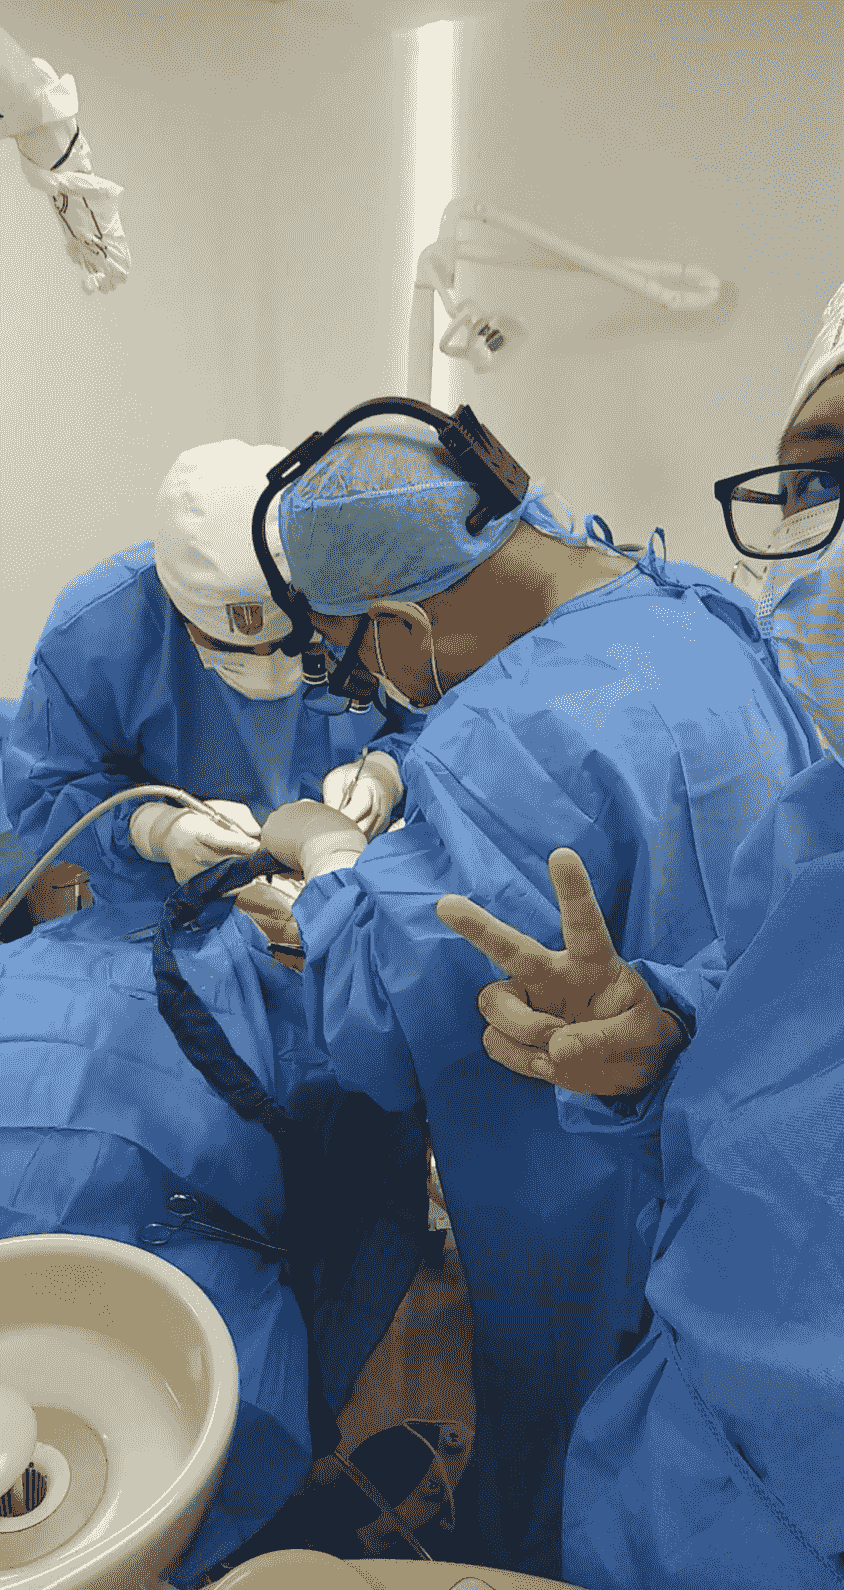

Nuestra Misión: Brindar Atención Dental Especializada

Abordamos cada caso dental con un enfoque personalizado, utilizando tecnología avanzada para garantizar resultados óptimos en el manejo de patologías periodontales e implantología. OFRECEMOS TRATAMIENTOS CON PRECIOS ACCESIBLES

Nuestro equipo de expertos está capacitado para manejar diversas patologías periodontales y procedimientos de implantología, asegurando atención de calidad en cada visita.Nuestros servicios especializados

Ofrecemos un amplio rango de tratamientos que abarcan desde la prevención hasta la rehabilitación avanzada.

Manejo de Patologías Periodontales

Expertos en el tratamiento de enfermedades como la periodontitis y gingivitis, así como en la realización de injertos de tejido blando y óseo, brindamos soluciones efectivas para tus problemas periodontales.

Implantes Dentales

Realizamos la colocación de implantes dentales con planificación computarizada, asegurando una integración óptima y duradera en tu boca, así como un seguimiento continuo para prevenir complicaciones.